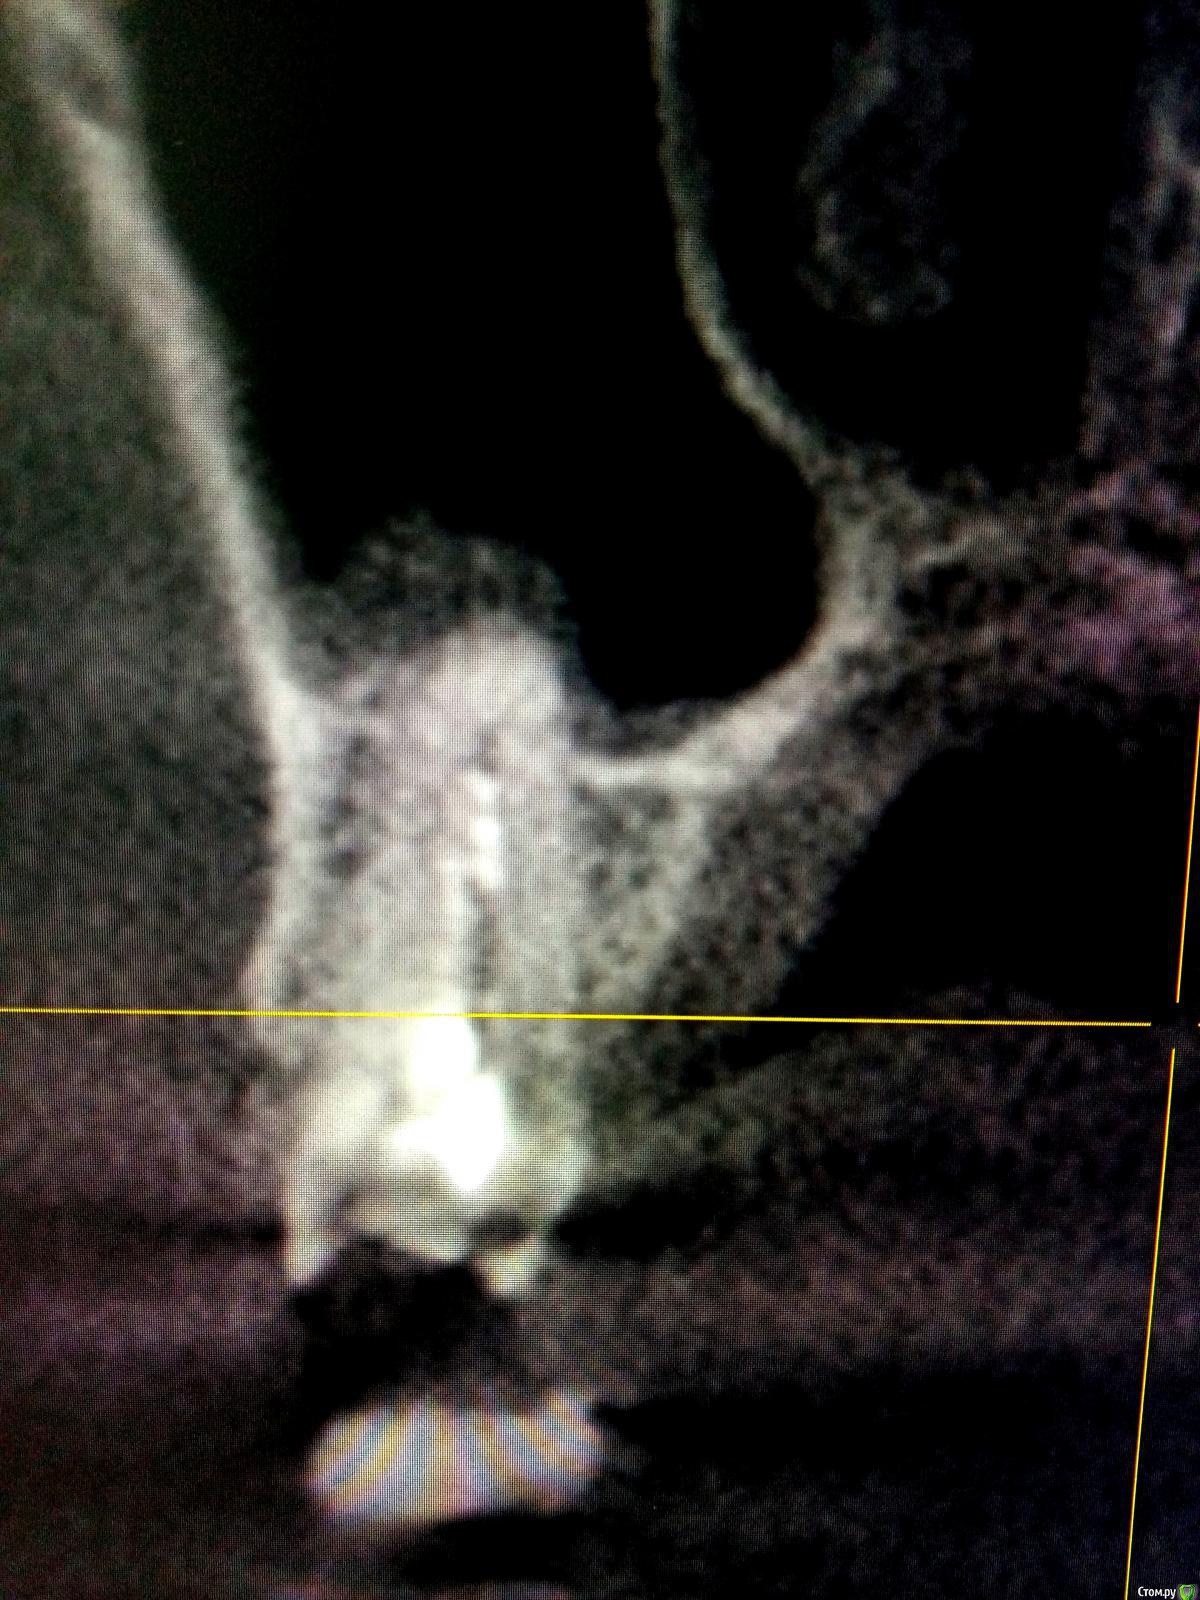

Raimar Опубликовано 18 ноября, 2019 Поделиться Опубликовано 18 ноября, 2019 Подскажите, как можно произвести эндодонтическое лечение? Нужно ли проходить дополнительные канальцы? Зуб 1.5 Ссылка на комментарий

Raimar Опубликовано 18 ноября, 2019 Автор Поделиться Опубликовано 18 ноября, 2019 Я так сначала и думал сделать,если честно), подскажите пожалуйста как можно пройти эти канальцы, у меня файлы упираются Ссылка на комментарий